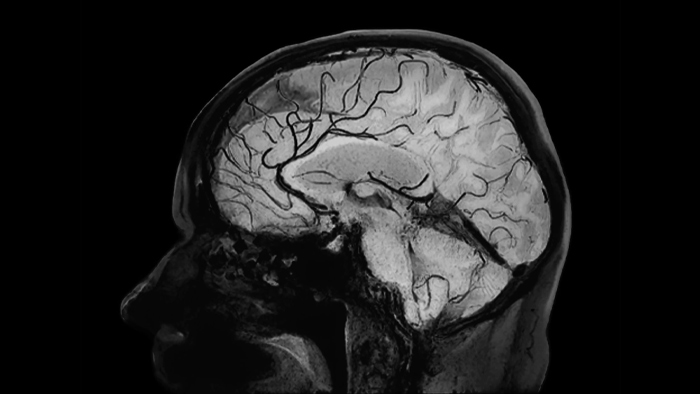

Black blood imaging

Clinical application

Brain